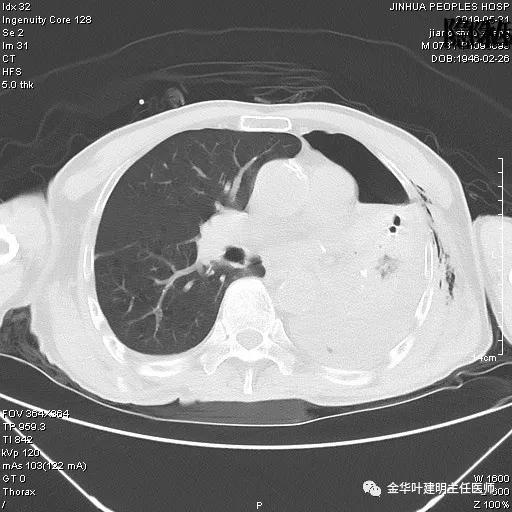

6.4上午:24小时引流出血性乳糜液1800毫升。是否再次手术进行右进胸胸导管结扎,抑或继续保守治疗非常纠结!压力非常大!!多方讨论会诊无法取得一致意见,但一般认为,引流量在1000毫升以上宜积极手术。情况与浙二医院范军强教授联系,请求指导,范教授认为左侧肺手术,损伤胸导管主干的机会较小,多数可保守治疗而愈。在他们的病例中,也有结扎胸导管后引流量仍无减少,效果并不能完全保证。建议可以考虑胸管夹管观察(因为淋巴管压力低,予以适当的压力,漏出量可能会明显减少),同时继续禁食,并静脉营养支持,引流管口可能会有渗液,注意更换敷料。与家属充分沟通后决定试夹管;这天血色素9.0 g/L;胸部CT复查示: